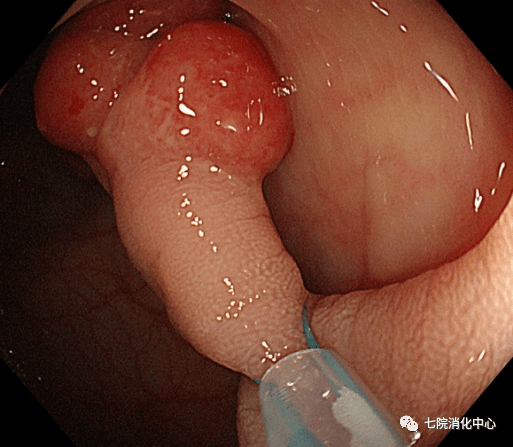

②冷圈套器:具有切除整个息肉的能力 , 避免了零碎的切除 , 并且可用于在同一过程中发现的较大息肉 。 其优点是可以防止电灼引起的对黏膜下血管组织的损害 , 并且对患者术后活动或饮食的限制较少 。 因为在冷圈套器息肉切除术期间不使用电灼 , 其术后出血和穿孔的发生率较低 。